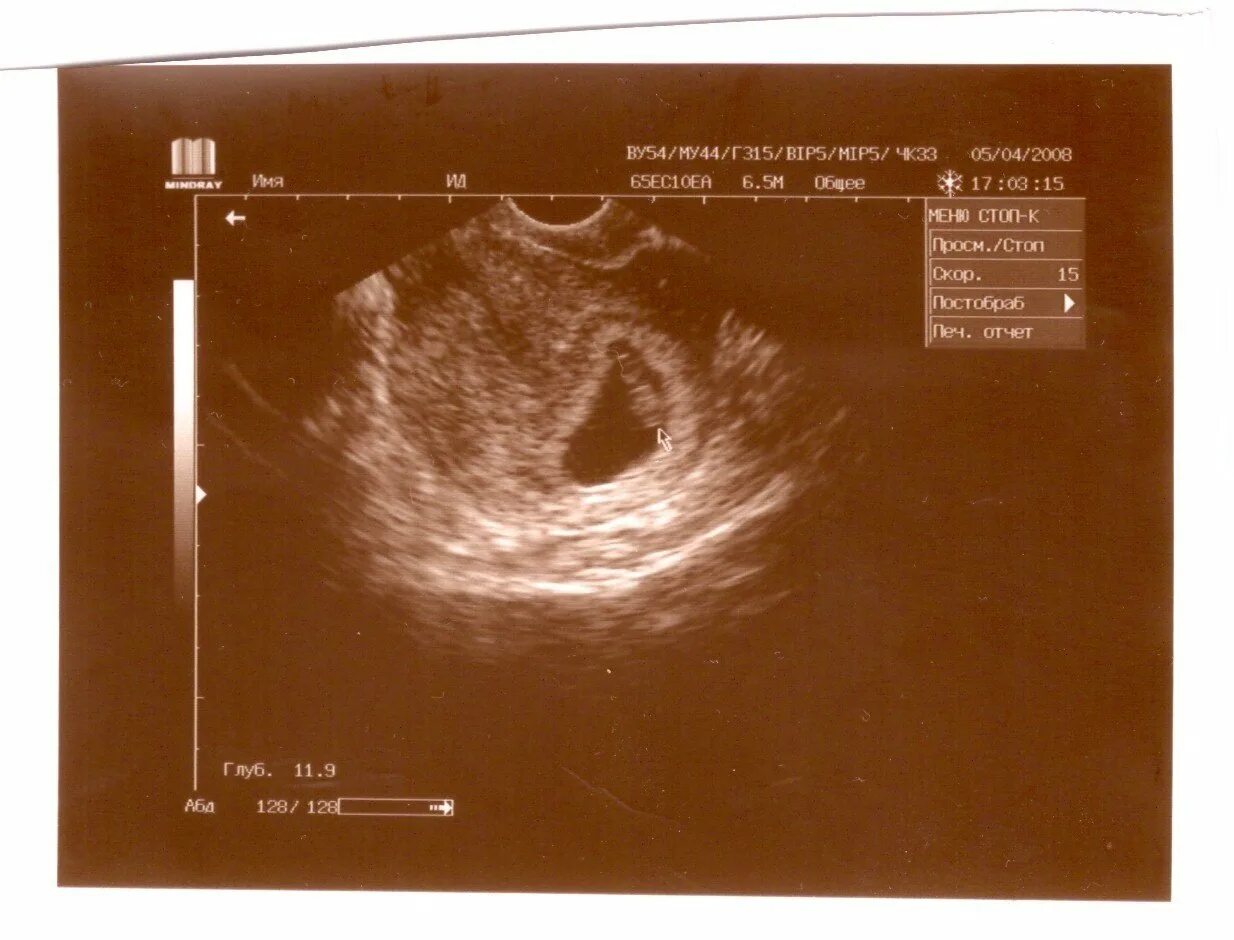

Тонус на ранних сроках форум